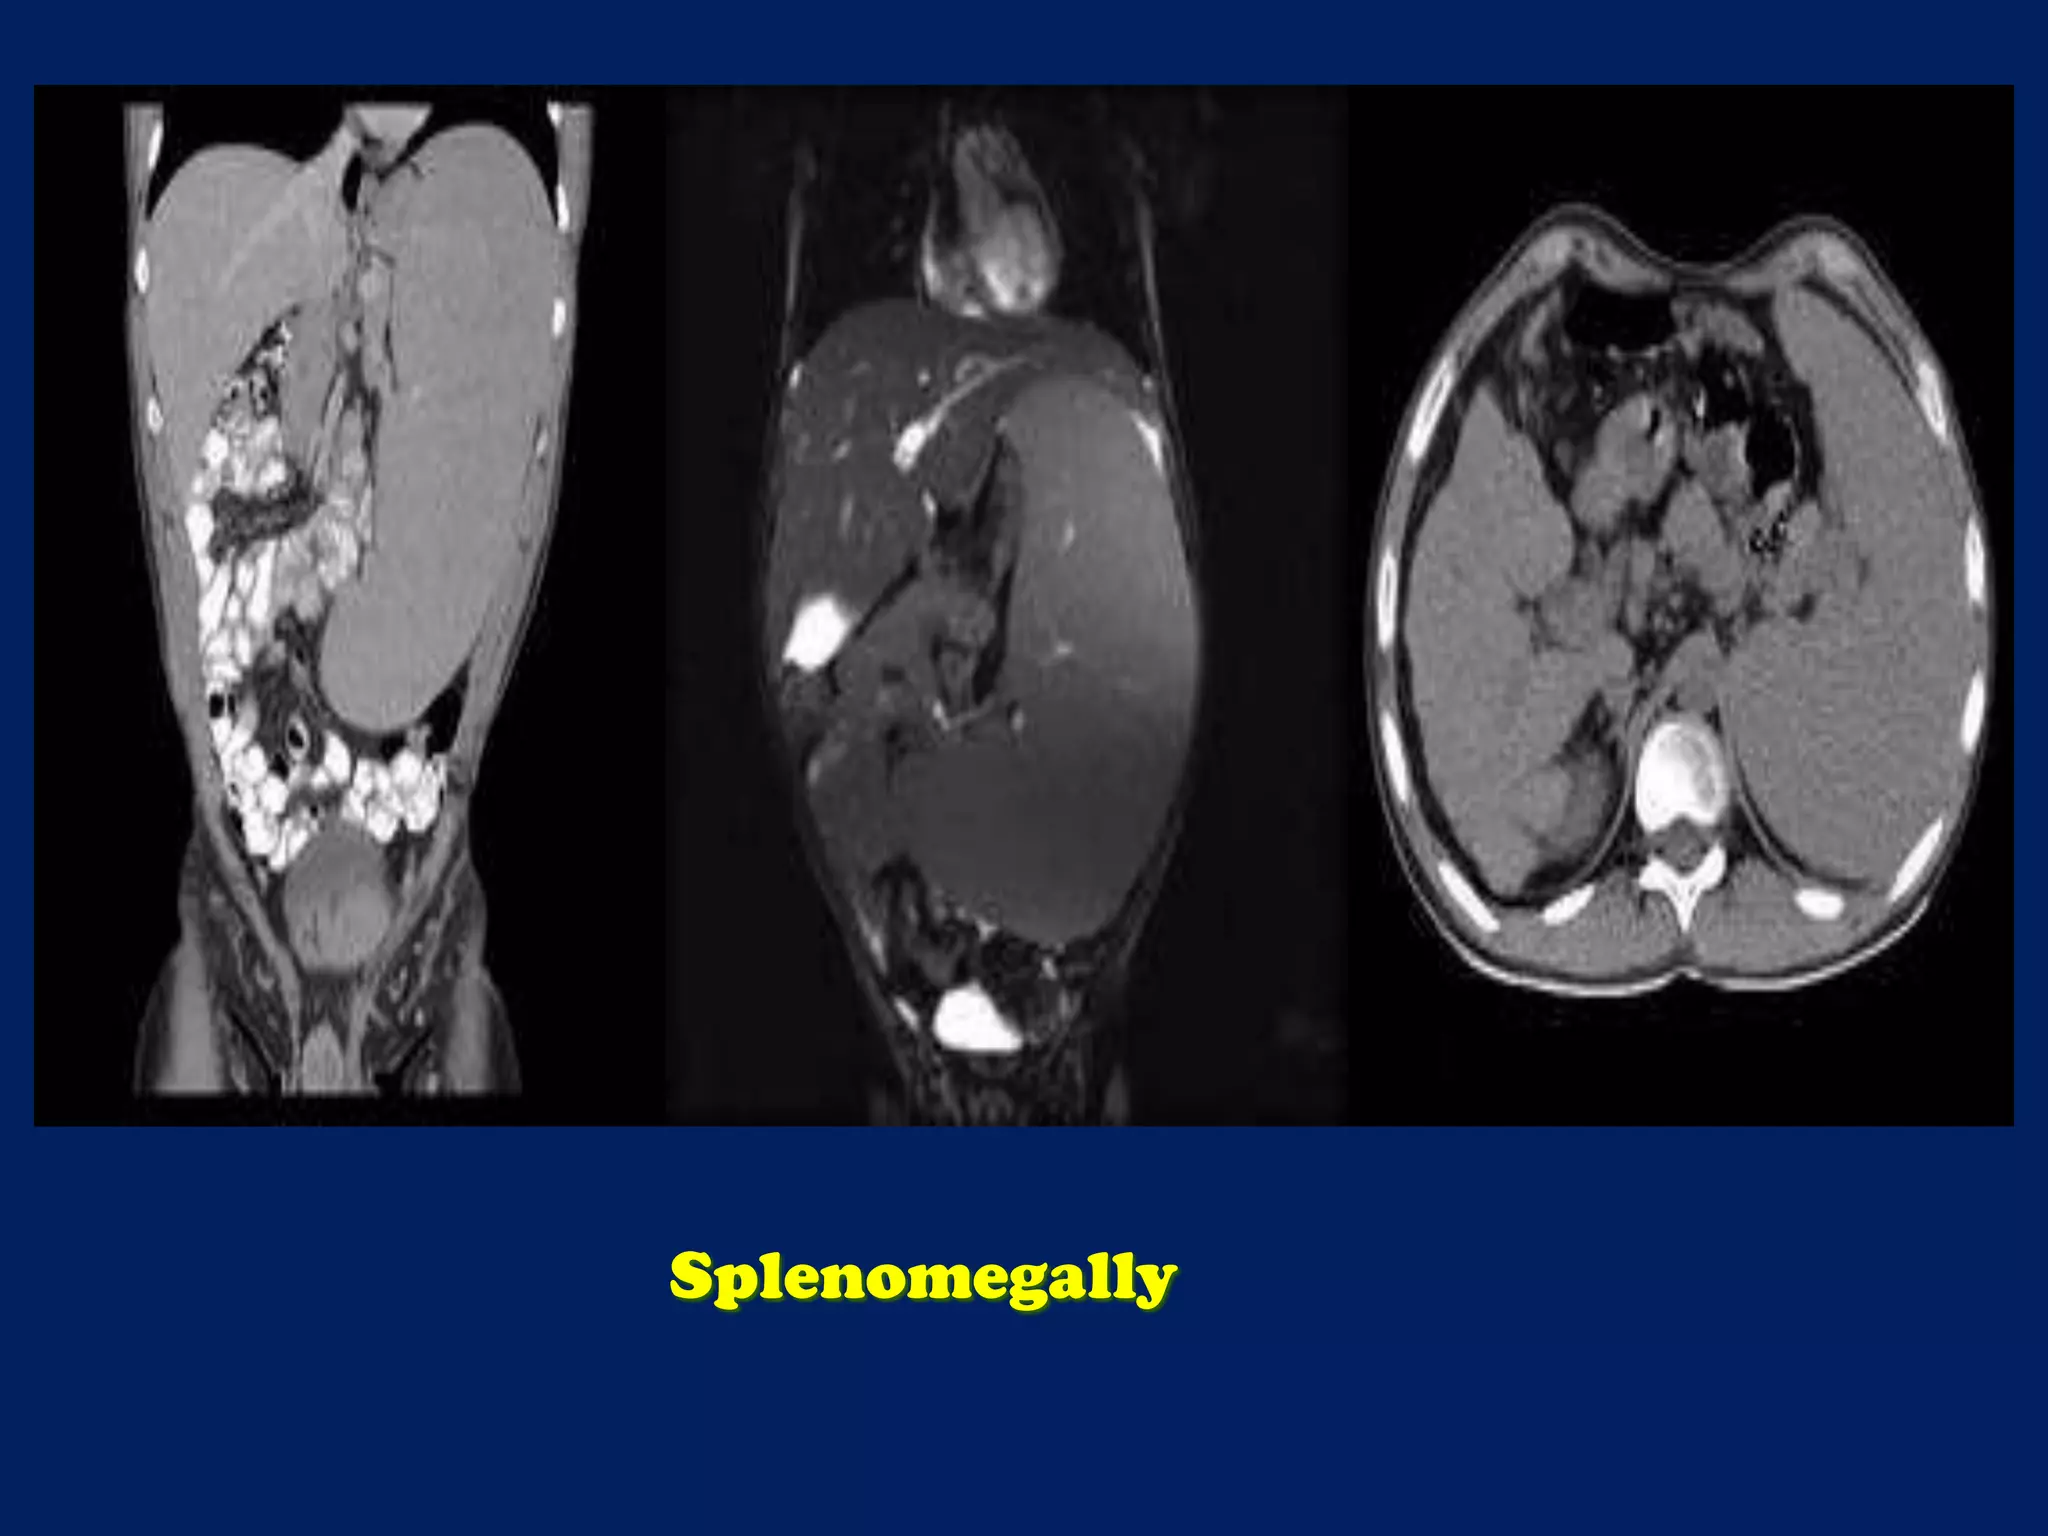

This document discusses imaging of the spleen and summarizes various congenital anomalies and pathologies that can affect the spleen. Some common congenital anomalies mentioned include accessory spleens, asplenia, polysplenia, and splenic fusions. Acquired conditions like repeated infarctions, infiltration, tumors, and cysts can also cause splenomegaly or functional asplenia. Wandering spleen is discussed as a rare congenital anomaly where the spleen lacks attachments and is mobile within the abdomen. Various grades of splenic lacerations and examples of splenic imaging findings are also briefly summarized.